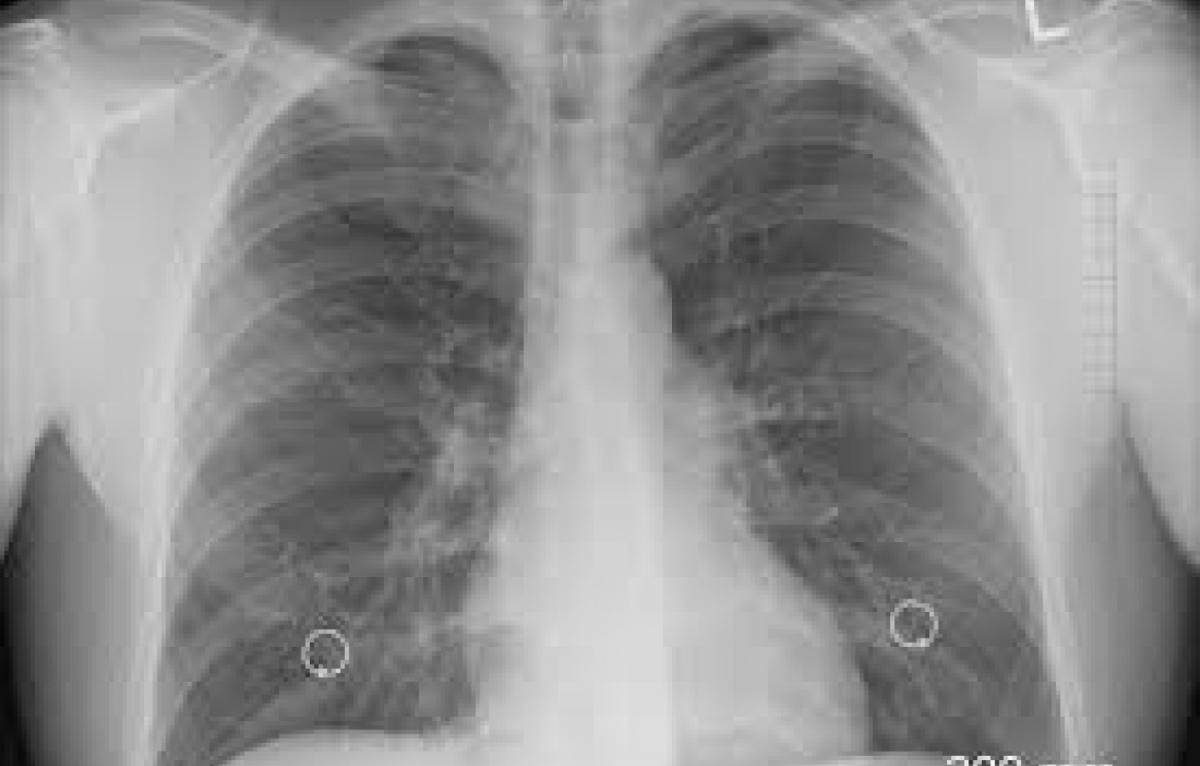

El cáncer de pulmón es la causa principal de muerte por esta enferemedad en el mundo. Cada año mueren 1.7 millones de personas con este diagnóstico, según la Agencia para la Investigación del Cáncer (IARC). Sus síntomas más conocidos son la tos persistente y el dolor torácico. Sin embargo, los especialistas advierten de un síntoma más desconocido.

Al igual que otros tipos de cáncer, el de pulmón comienza cuando células anormales crecen sin control en este órgano. En un comienzo los signos pueden ser leves o descartarse como problemas respiratorios comunes, lo que algunas veces puede retrasar el diagnóstico.